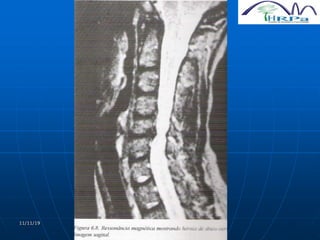

HÉRNIA LOMBAR

 Mais freqüente hérnia de disco

 Modic (1986) demonstra que a RNM apresenta a

melhor avaliação dignóstica do que a mielografia

e a TC